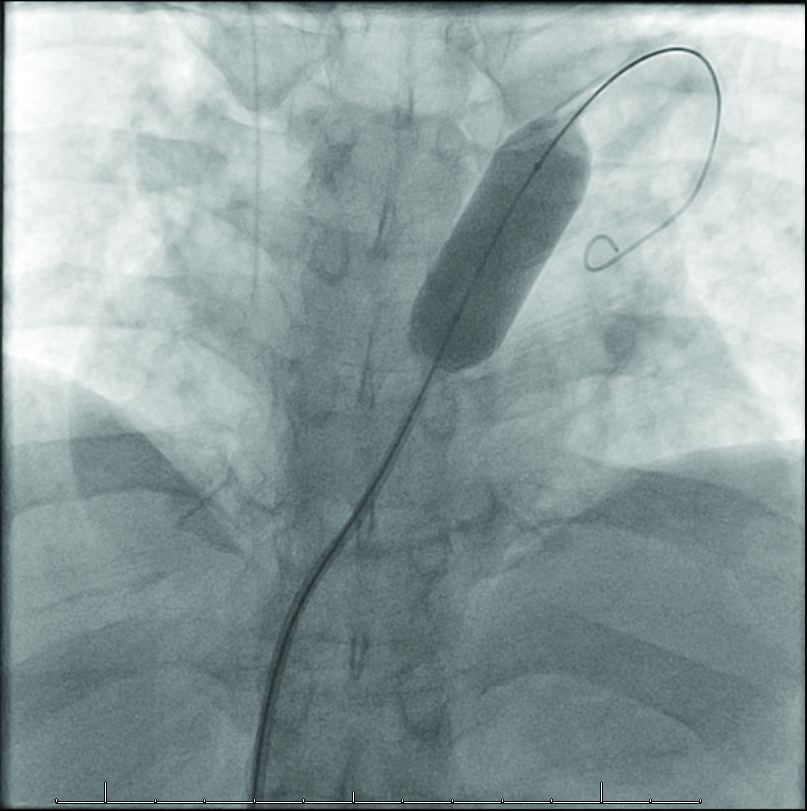

Further workup included a TTE that showed no acute abnormality and a stable pulmonic valve without any signs of insufficiency. But shunting was suspected, and a bubble study showed a secundum ASD with large right to left shunt (Figure 3). A transesophageal echocardiogram (TEE) showed only trace tricuspid regurgitation and a large fenestrated ostium secundum ASD with bidirectional shunt (Figure 4).

Figure 3

Figure 3. Bubble study with a four-chamber view showing significant right to left shunt across atrial septum.